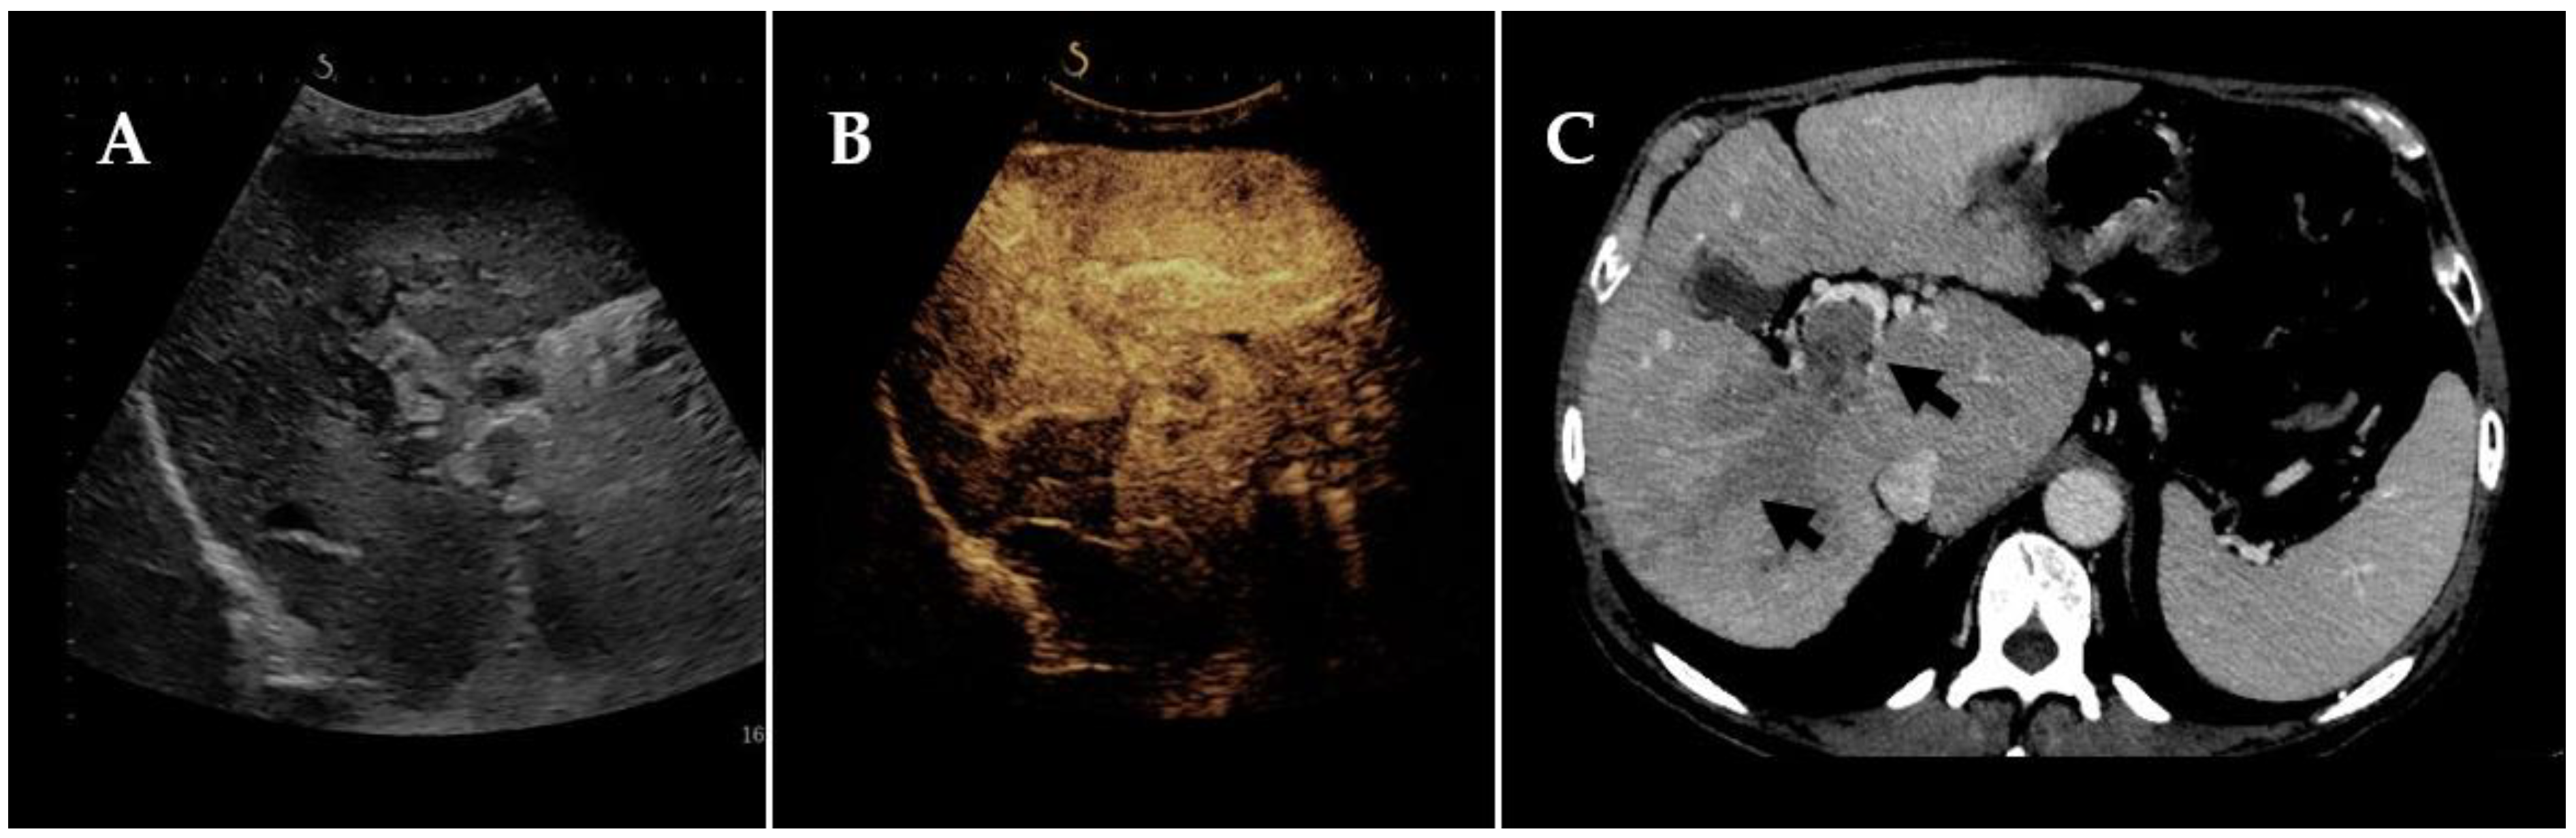

- Burciu, C.; Șirli, R.; Bende, F.; Fofiu, R.; Popescu, A.; Sporea, I.; Ghiuchici, A.M.; Miuțescu, B.; Dănilă, M. Usefulness of Imaging and Biological Tools for the Characterization of Portal Vein Thrombosis in Hepatocellular Carcinoma. Diagnostics 2022, 12, 1145. [Google Scholar] [CrossRef]